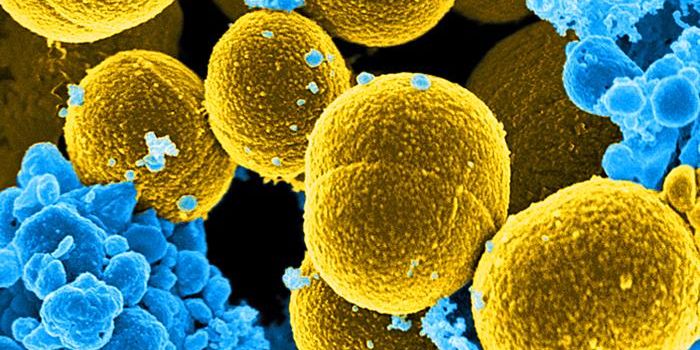

SEP 17, 2021Cell & Molecular BiologyMRSA (methicillin-resistant Staphylococcus aureus) is a well known superbug, a pathogenic microbe that can cause serious ...